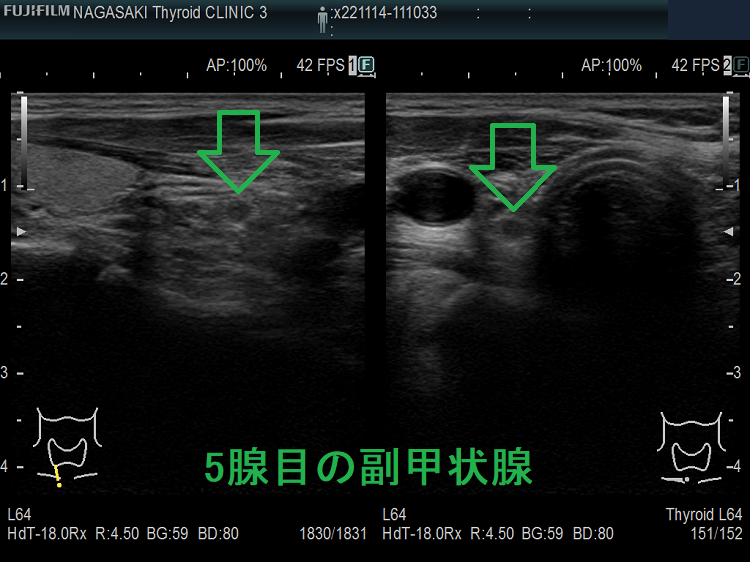

高カルシウム血症の程度と副甲状腺腫の大きさは必ずしも比例しない